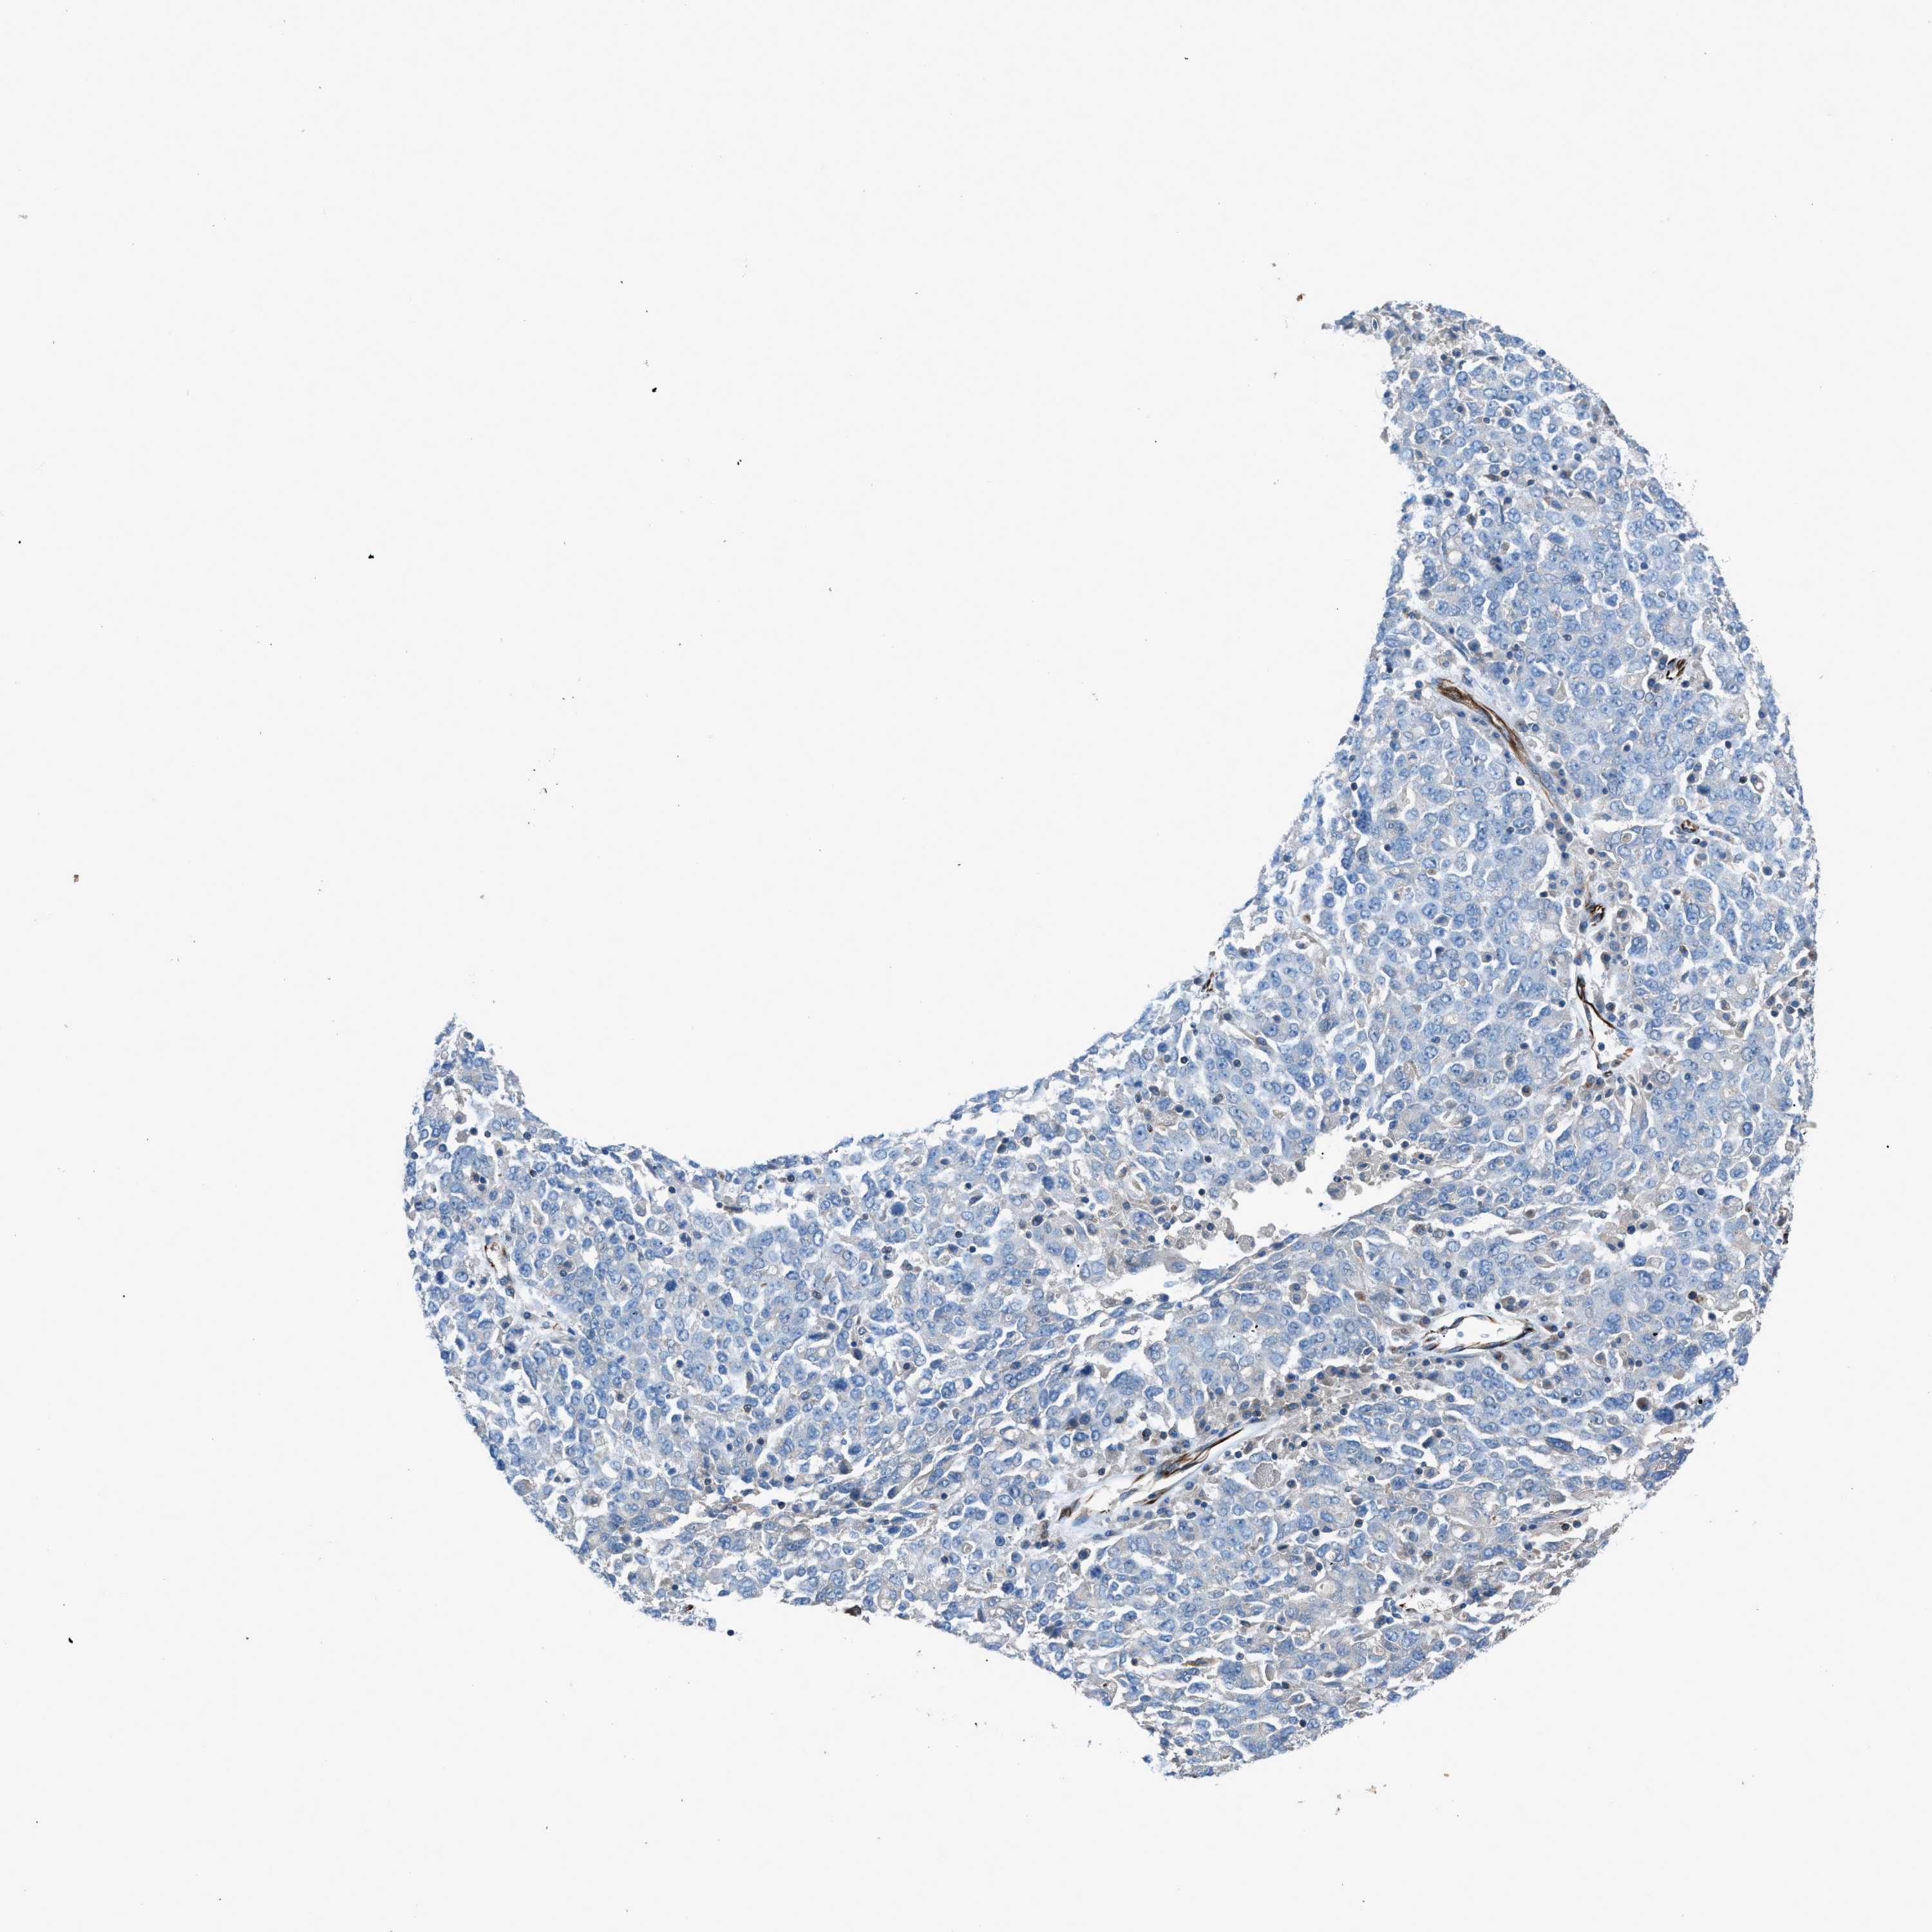

OVARIAN CANCER - Protein expressioni

A mouse-over function shows sample information and annotation data. Click on an image to view it in a full screen mode. Samples can be filtered based on level of antibody staining by selecting one or several of the following categories: high, medium, low and not detected. The assay and annotation is described here.

Note that samples used for immunohistochemistry by the Human Protein Atlas do not correspond to samples in the TCGA dataset.

Antibody stainingi

Antibody staining in the annotated cell types in the current human tissue is reported as not detected, low, medium, or high, based on conventional immunohistochemistry profiling in selected tissues. This score is based on the combination of the staining intensity and fraction of stained cells.

Each image is clickable and will lead to virtual microscopy that enables deeper exploration of all samples and also displays staining intensity scores, fraction scores and subcellular localization as well as patient and tissue information for each sample.

Antibody HPA016439

Staining

High

Medium

Low

Not detected

Intensity

Strong

Moderate

Weak

Negative

Quantity

>75%

75%-25%

<25%

None

Location

Nuclear

Cytoplasmic/membranous

Cytoplasmic/membranous,nuclear

Cystadenocarcinoma, serous, NOS

Carcinoma, endometroid

Cystadenocarcinoma, mucinous, NOS

Carcinoma, NOS